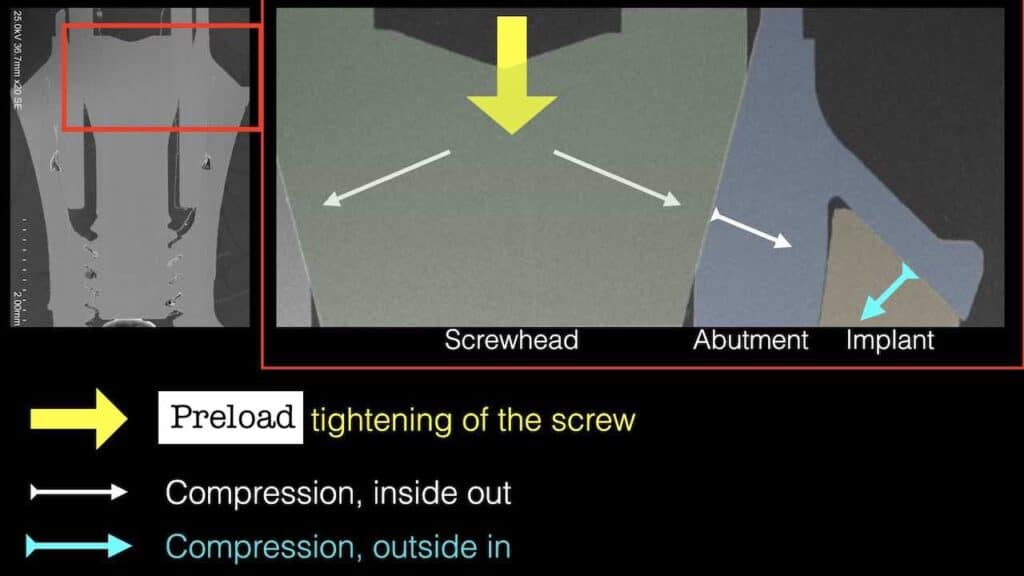

Studying the Synocta connection of the Straumann Tissue Level implant, one can easily see how solid and stable this configuration is. There is an element of this connection that is impossible to imitate at bone level implants and this is the “double squeeze” of the abutment between the oblique head of the abutment screw and the external part of the prosthesis that rests on the oblique implant shoulder. As we tighten the screw, the oblique head presses the abutment outwards against the implant wall. At the same time, the part of the abutment resting on the oblique implant shoulder presses the implant wall inwards, just like the ring of a barrel. The stability of this configuration to lateral forces is unparalleled by any platform switching connection, where inevitably the abutment can only be wedged internally and press outwards. At the same time, the 2.8 mm high collar of the tissue level implant will bring the fulcrum of any lateral forces much more coronally than in Bone Level implants reducing the damaging effect on the connection.

The “double squeeze” of the Synocta connection at the Tissue Level implant as seen under the Scanning Electron Microscope (Mattheos, Larsson, Janda et al 2017). Note how the abutment shoulder is compressing the connection inwards, adding stability on the oblique implant shoulder.